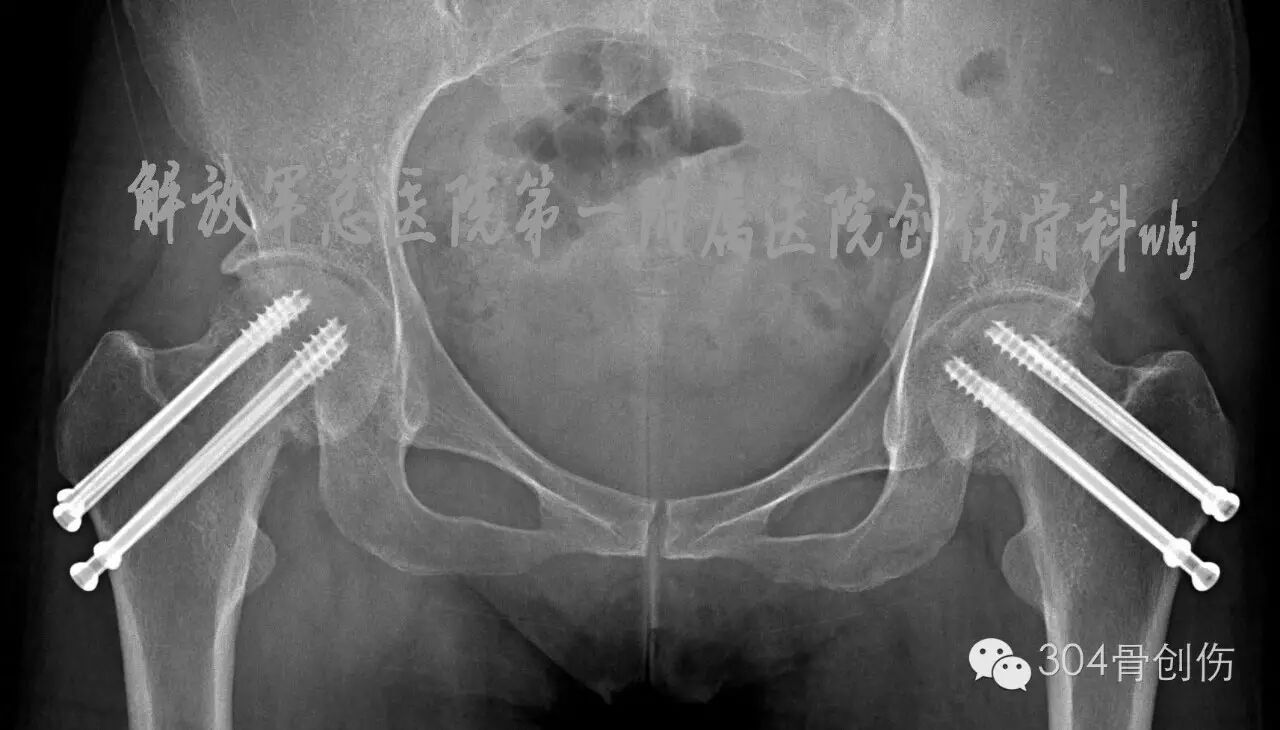

女,31岁,主因“双侧髋部疼痛活动受限6周”就诊。病史:患者孕36周时,扭伤跌倒,双髋部疼痛,活动受限,不能站立。X线显示:双侧股骨颈骨折,暂行保守治疗,待分娩后处理骨折。孕39周剖腹产一男婴,产后3周入304创伤骨科治疗。入院查体:体重50kg,身高156cm,双下肢外旋畸形,双大腿近端前外侧压痛,双下肢纵向叩击痛阳性,诊断:双侧股骨颈陈旧性骨折(Garden Ⅳ型-图)。

图-患者伤后X线片

(盆腔内为胎儿头颅)

治疗经过

全麻下双侧股骨颈骨折闭合复位内固定。在C型臂透视下,牵引床辅助闭合复位,固定股骨头、下肢极度内旋,骨折复位满意,为增加固定强度,双侧各经皮打入4枚空心螺钉(图)。术后口服钙尔奇600mg每天2次,骨化三醇胶丸0.25ug 每天3次。双腿非负重活动。